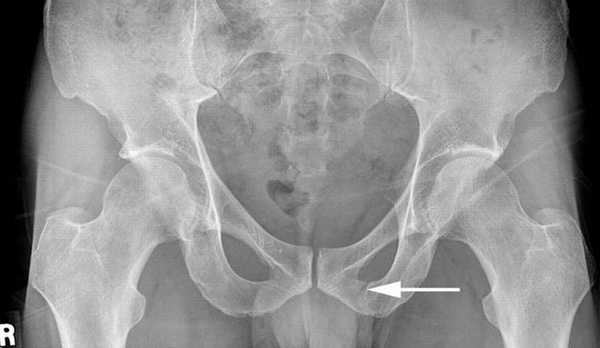

Перелом лонной кости

- Переломы и трещины. На рентгене можно рассмотреть локализацию травмы, наличие смещения и количество отломков и осколков, степень смещения костных структур.

- Вывихи. Визуализируется выход большого вертела бедренной кости из суставной поверхности вертлужной впадины.